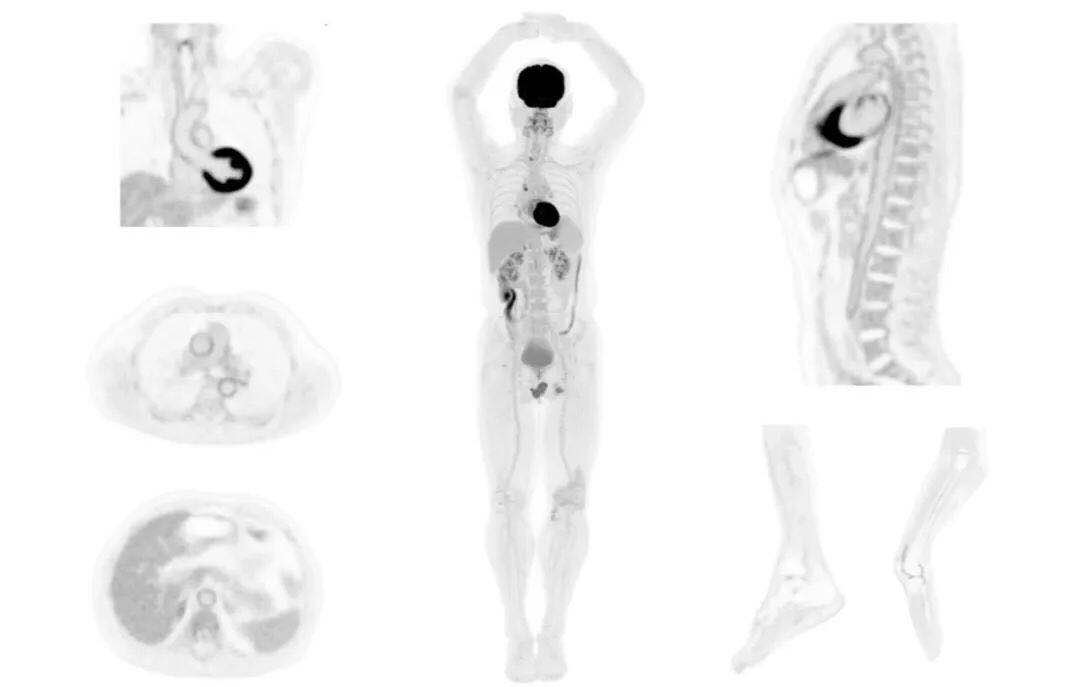

肺癌轉(zhuǎn)移及復(fù)發(fā)

患者男性,66歲,七年前發(fā)現(xiàn)右肺肺癌,其間手術(shù)兩次,共切除兩個(gè)肺葉,復(fù)查;

診斷意見(jiàn),回腸轉(zhuǎn)移,右肺殘留部復(fù)發(fā)